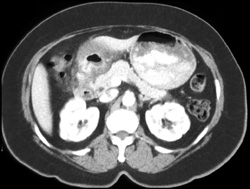

Gastric Varices